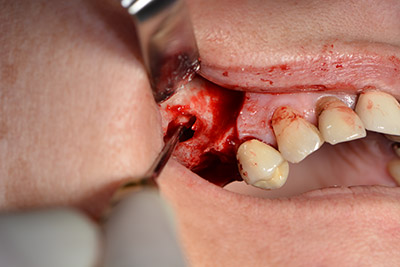

Danach wird das Implantat eingebracht und der Knochen aufgebaut. Aufgrund der Größe des Augmentates wurde im vorliegenden Fall Eigenknochen, der als Bohrspäne bei der Implantation 16 und der Fenestration 14 angefallen ist und mit einer Knochenfalle aufgefangen wurde, mit Knochenersatzmaterial vermischt.

Eine resorbierbare Membran bildet die Barriere nach bukkal und deckt das Augmentat ab. Zum Schluss wird speicheldicht vernäht. (Abb. 15 bis 19).

speicheldichter Wundverschluss.

Abb. 19